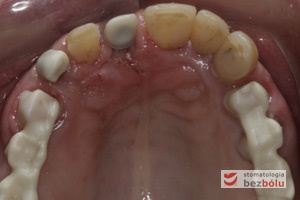

Powierzchnie okluzyjne górnego łuku zębowego - zęby szczęki przygotowane zachowawczo do dobudowy implanto-protetycznej

Powierzchnie okluzyjne górnego łuku zębowego – zęby szczęki przygotowane zachowawczo do dobudowy implanto-protetycznej